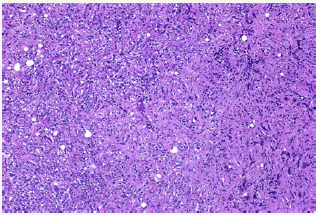

Figure 8: Tumour cells having round, irregular cleaved nuclei with prominent nucleoli and moderate amount of cell cytoplasm with frequent mitotic figures suggestive of round cell tumour.

A 58 year old female presented with pain in the left thigh and pelvis. She was originally radiographed (Figure 1 & 2) and was managed conservatively in the periphery. The radiographed of the skull showed no involvement of skull bones (Figure 3).Then the MRI of the femur and pelvis was done which reported it is as a cystic lesion and was advised extended curettage (Figure 4 & 5). No treatment was done. Two months after this the patient presented to us with greater pain and a pathological fracture left trochanteric region. The patient also had palpable subcutaneous masses in the head. We reviewed the MRI and did CECT pelvis and CECT head. CECT pelvis showed lytic expansile destruction of both the sacral ala with soft tissue masses extending into spinal canal causing compression of the cal sac in addition to the original lesion in the neck and trochanteric region with fracture (Figure 6). CECT head showed multiple lytic areas with formation of soft tissue masses in extra-calvirial and intra cranial locations (Figure 7). The brain parenchyma was normal. We did biopsy of the trochanteric region and nodule from scalp. Both the reports showed large tumour cells having round, irregular cleaved nuclei with 1-2 prominent nucleoli and moderate amount of cell cytoplasm with frequent mitotic figures (Figure 8). On immunohistochemistry were positive for LCA and CD-20 suggesting diffuse large B- cell lymphoma (Figure 9). The patient was then started on CHOP regime.

In terms of anatomic involvement the most common site arefemur(27%), pelvis(15%), tibia/ fibula(13%), polyostotic(13%), humerus(12%), spine(9%), skull(1%) etc as reported by Beal et al. with a male-female ratio of 1.5:1 and a median age of 48 years [6]. Radiologically bony lesions may be extensive, destructive or infiltrative. Extensive lesions involve 25-50% of affected bone, sometimes entire bone. Destructive lesions are radiolucent, mottled, patchy, moth eaten and sometimes the outline of the bone is completely lost. Infiltrative or permeative lesions have poorly defined interface with normal bone, 50% have a mixture with small areas of sclerosis. Nearly all variants destroy cortical bone and 25% thicken the cortex. Often large, obvious soft-tissue extension may be present along with bony lesion [7]. Diagnosis is established by biopsy. The tumor cells are positive for CD45, CD20, CD79a, LCA and negative for CD3 and CD5 [8].